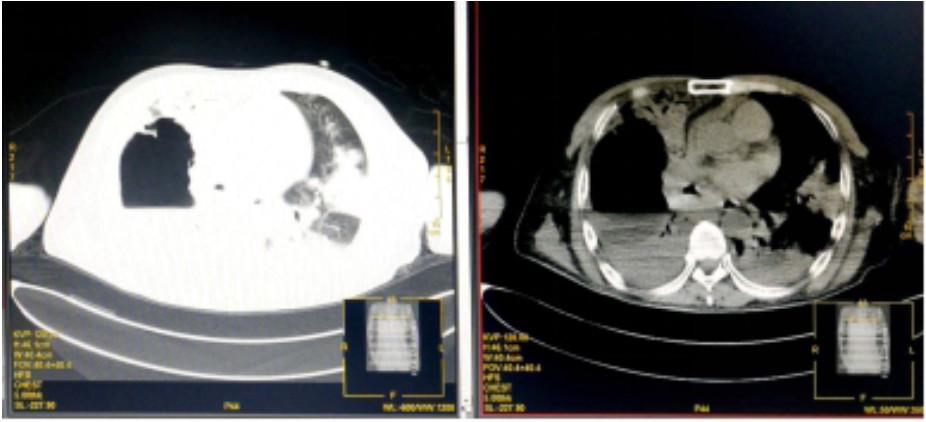

入院诊断“社区获得性肺炎”。予无创呼吸机支持(FiO2 75%),经验性予以美罗培南静脉泵入1.0 g 2次/d、磷酸奥司他韦口服75 mg 2次/d、莫西沙星静脉滴注0.4 g 1次/d。入科后治疗4 h仍无尿,且呼吸困难进行性加重,血氧饱和度进行性下降,氧合指数109 mmHg,予以经口气管插管接呼吸机辅助通气及连续性血液净化等治疗。机械通气后,吸出大量灰褐色痰,且病情进展快,短时间无法脱机拔管,12月17日气管切开。12月17日复查血常规:血白细胞2.49×109/L,中性粒细胞百分比0.925,血红蛋白70 g/L,血小板62×109/L。停用莫西沙星改用利奈唑胺0.6 g静脉滴注2次/d。12月19日胸部CT示,⑴双肺散在多发感染性病变,右侧为著;⑵右肺空腔伴气液平;⑶右侧胸腔积液(图 2)。12月19日血白细胞3.7×109/L,中性粒细胞百分比0.882,淋巴细胞百分比0.098,血红蛋白78 g/L,血小板115×109/L,入科后立即送检的血、痰培养回报均阴性。12月20日肺泡灌洗液病理回报镜下见炎症细胞、吞噬细胞及菌丝样物,未发现恶性细胞(图 3)。12月21日痰宏基因组学检测回报:肺炎链球菌(序列数113 916)、屎肠球菌(序列数1 307)、铜绿假单胞菌(序列数16)。12月20日及24日肺泡灌洗液、血培养均回报为屎肠球菌,药敏试验结果示,对氨苄青霉素、环丙沙星、红霉素、庆大霉素、青霉素耐药;对替考拉宁、替加环素、利奈唑胺、万古霉素、奎奴普丁/达福普丁敏感。继续利奈唑胺600 mg 2次/d,总疗程62 d。治疗期间血红蛋白在66~91 g/L,血小板均在(100~300)×109/L。12月26日CT引导下经皮肺组织穿刺术,并送检病理细胞学及组织培养,结果显示符合炎症性病变改变,病原学阴性。2020年1月9日脱离呼吸机,1月14日转入普通病房,1月23日拔出气管切开套管,2020年2月13日复查胸部CT病灶有所吸收(图 4),2月24日好转出院。出院半年后电话随访,当地医院复查胸部CT示病灶较前明显吸收,已经正常工作。

| 图 4 2020年2月13日胸部CT结果(双肺多发异常密度,右侧为著伴右肺空洞,较前有所吸收;双侧胸腔积液,右侧较前有所减少,左侧较前稍有增多) |